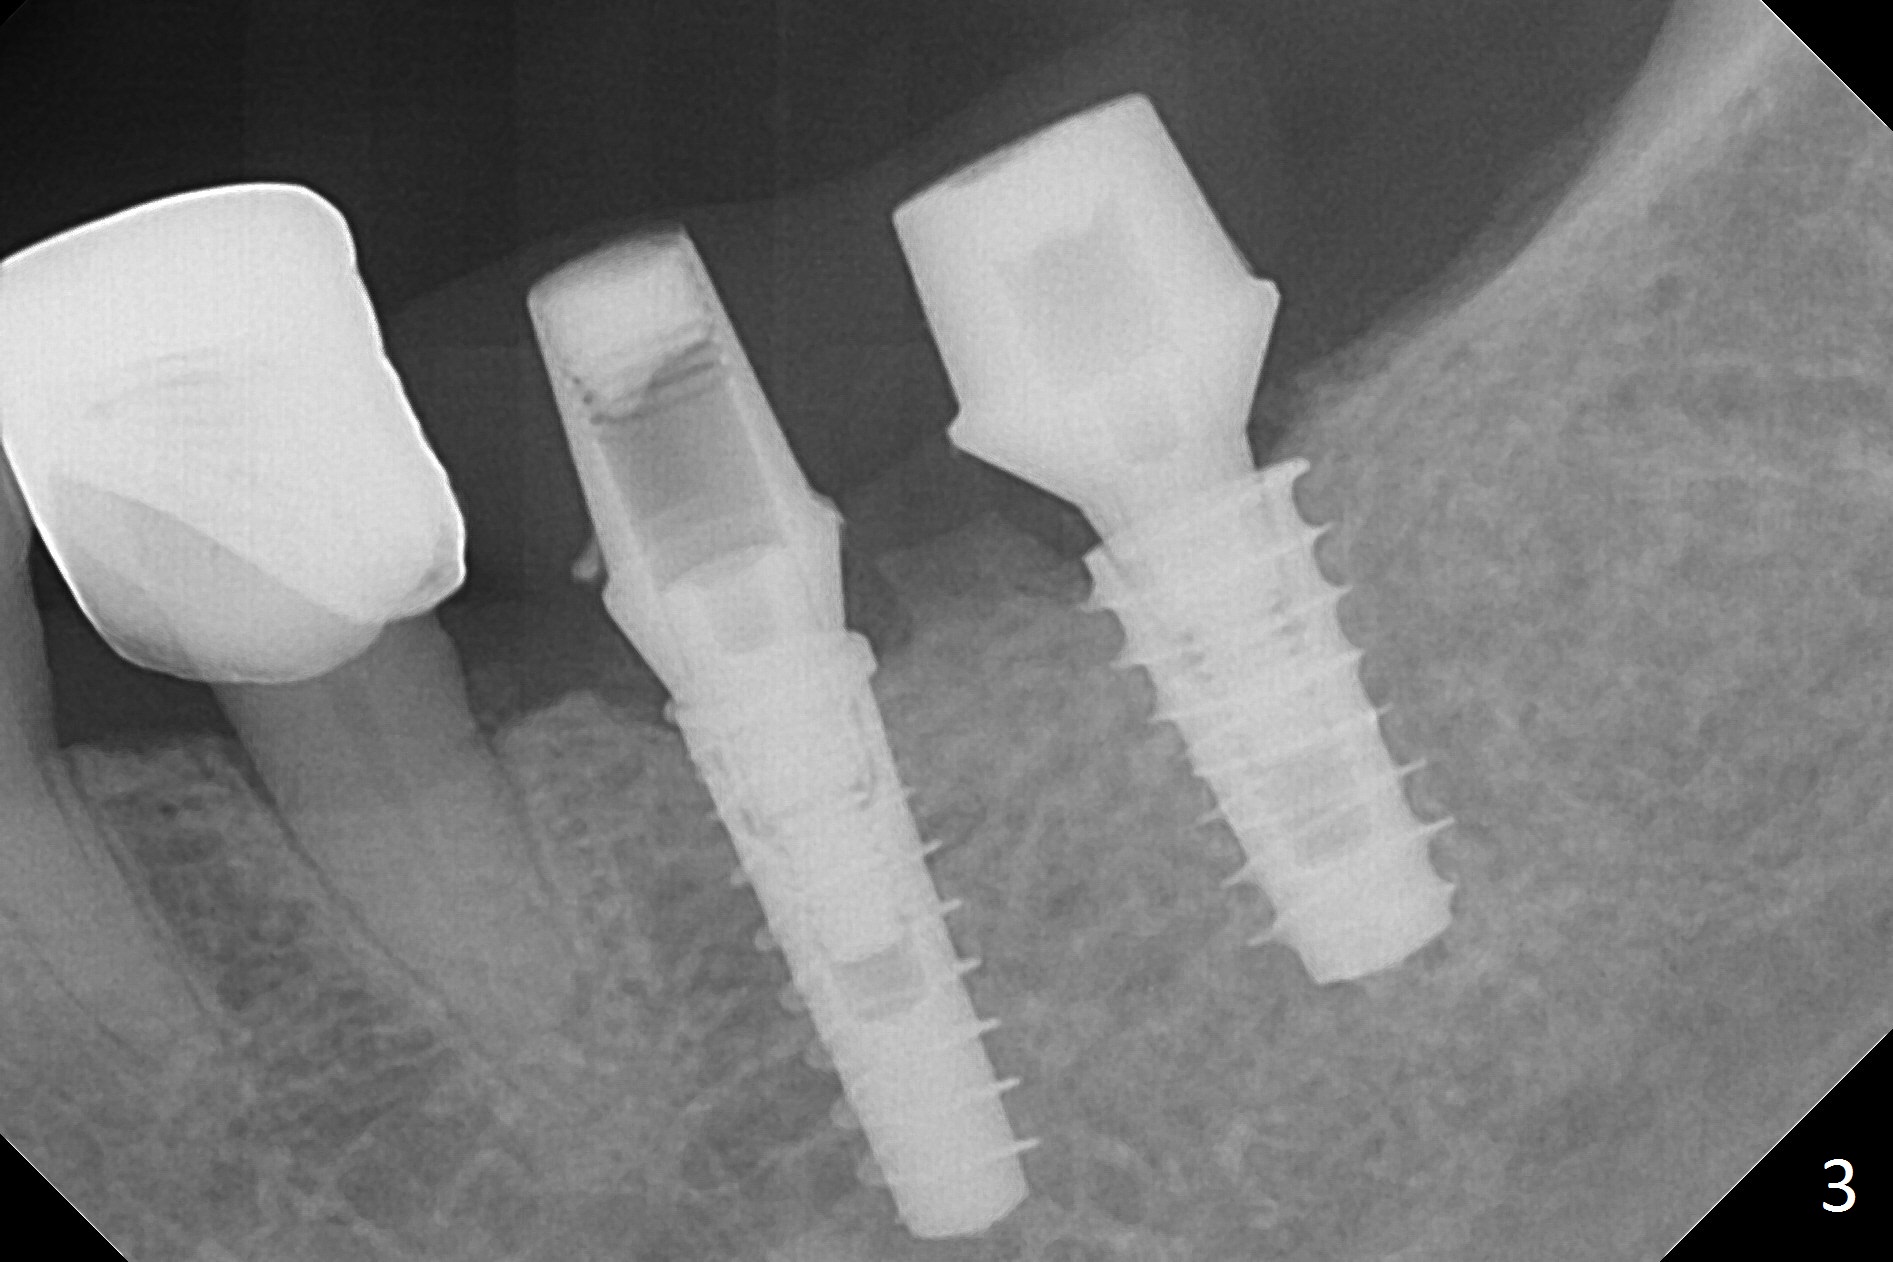

Because of the narrow ridge top at the sites of #19 and 18, it is reduced (Fig.1 arrowheads) prior to initial osteotomy with 1.6 mm pilot drill.  After Magic Drills (3.3 and 4.3 mm at #19 and 18, respectively), 4x11 and 5x9 mm IBS implants are placed with insertion torque >35 Ncm with immediate placement of pair abutments (4.5x5.7(2) and 6.5x4(2) mm, Fig.2).  In fact these sites are converted to a premolar and a 1st molar (because narrow ridge at #19).  Following GBR and suturing, periodontal dressing is applied around the abutments for increased retention.  The regional ridge reduction makes Marking Bur unnecessary (because of flat ridge top and the soft bone in this case) and more importantly there is no thread exposure upon implant placement.  The trimmed site (concavity) is favorable for bone graft and membrane placement.  One month postop, loose perio dressing is removed and replaced by a splinted nonfunctional provisional.  The implant sites look normal nearly 3 months postop; there is no bone loss (Fig.3).  Impression is taken.  The crown/abutment at #18 is loose 3 years 2 months post cementation; when the crown/abutment is retightened, the abutment remains incompletely seated (Fig.4 <) in spite of reduction of the proximal contact (arrow).  It may be due to the block of the distal crest (*).  After use of 5.5 mm profile drill, the 6.5x4(2) mm abutment remains unseated (Fig.5).  The smaller one (5x4(2) mm, Fig.6) is seated.  When the redo crown is cemented, the surrounding gingiva is healthy with a short papilla between the implant crowns (Fig.7).